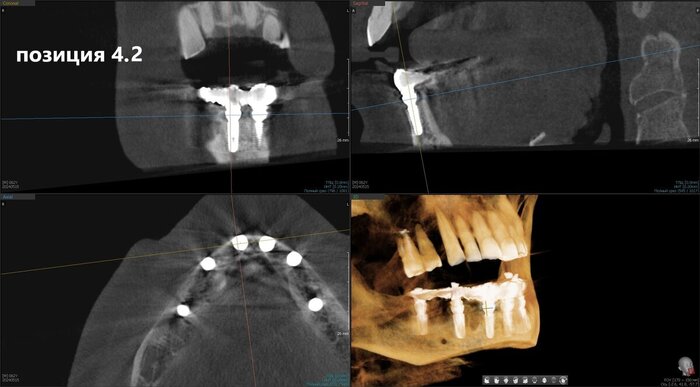

Имплантаты установлены и пациент отправляется на КЛКТ. Каждый раз очень радуется имплантолог, что аппарат находится в клинике. Я тоже рада)

Позиция 4.6

Имплантолог видит, сколько мм можно докрутить безопасно для структур челюсти (нервов, сосудов). Делает дело.

Сделали КЛКТ:

КЛКТ